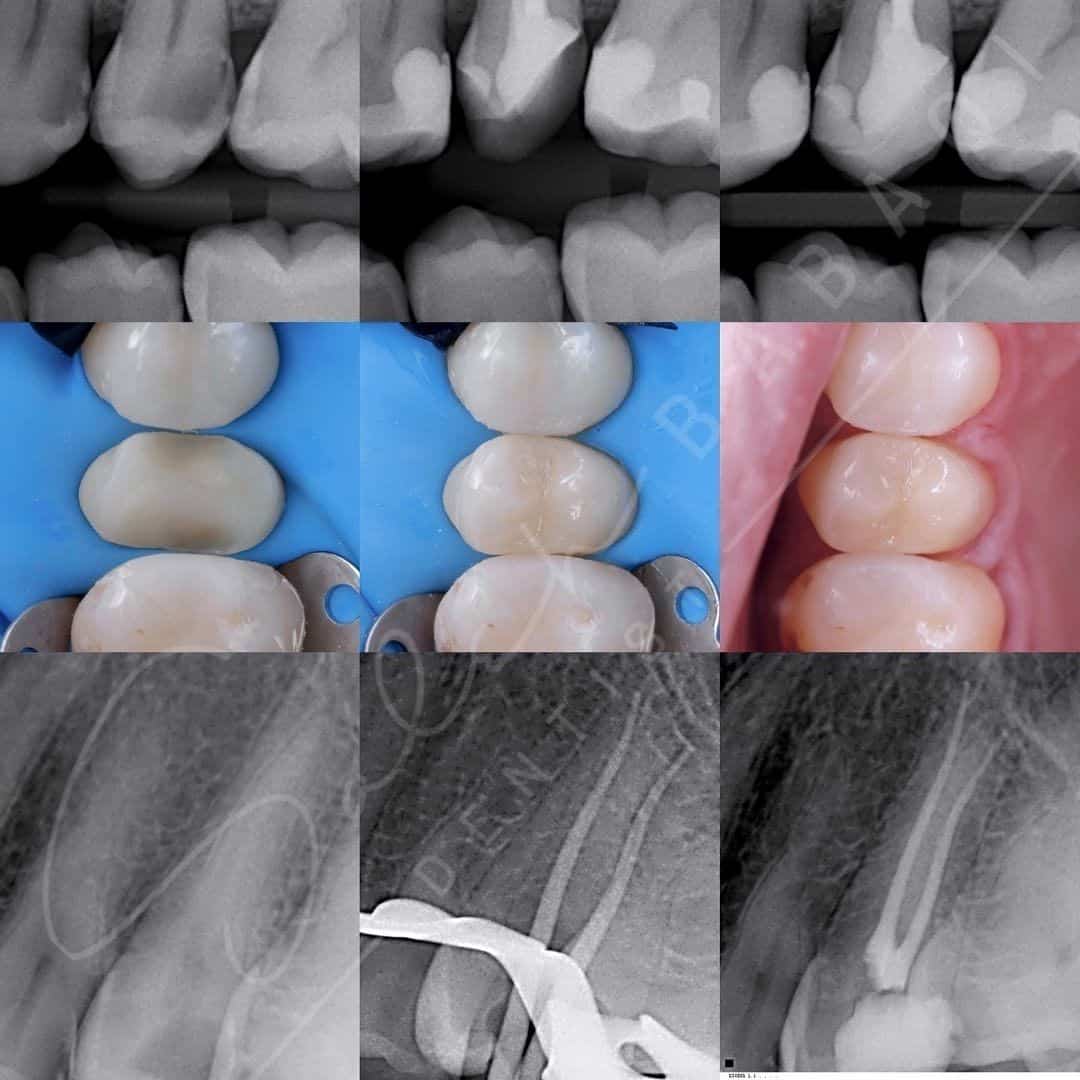

نتائج رائعة لمراجعينا